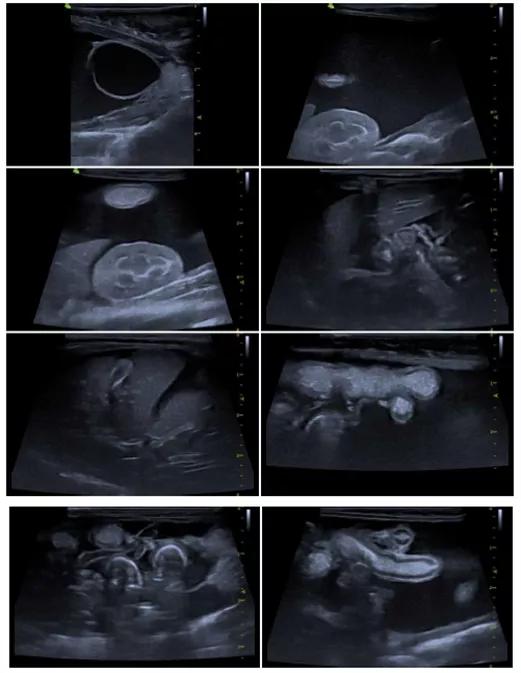

超声提示:腹水,腹膜炎,脂肪肝。

超声一月后复查腹水消失,淋巴结较上次检查减小,双肾髓质环症